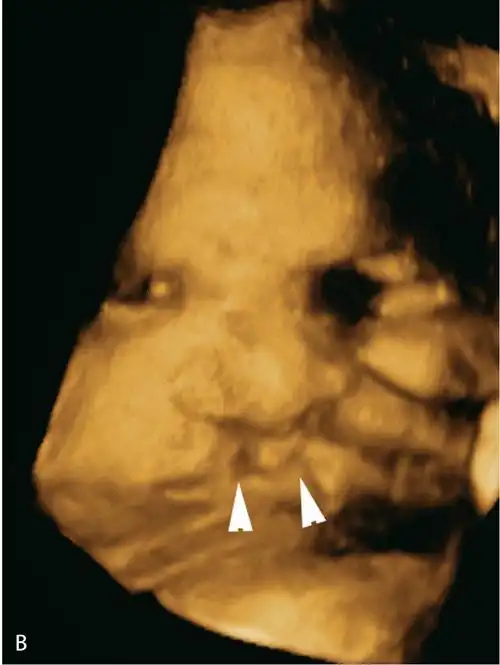

1.3双侧唇裂.(b)同一胎儿的三维图像显示双侧唇裂(三角箭头).图6.1.